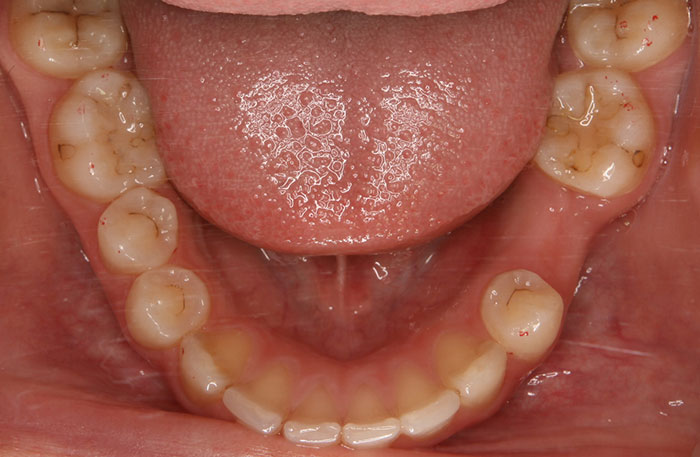

歯の移植の症例

Before

After

歯の移植をしたレントゲン写真です。